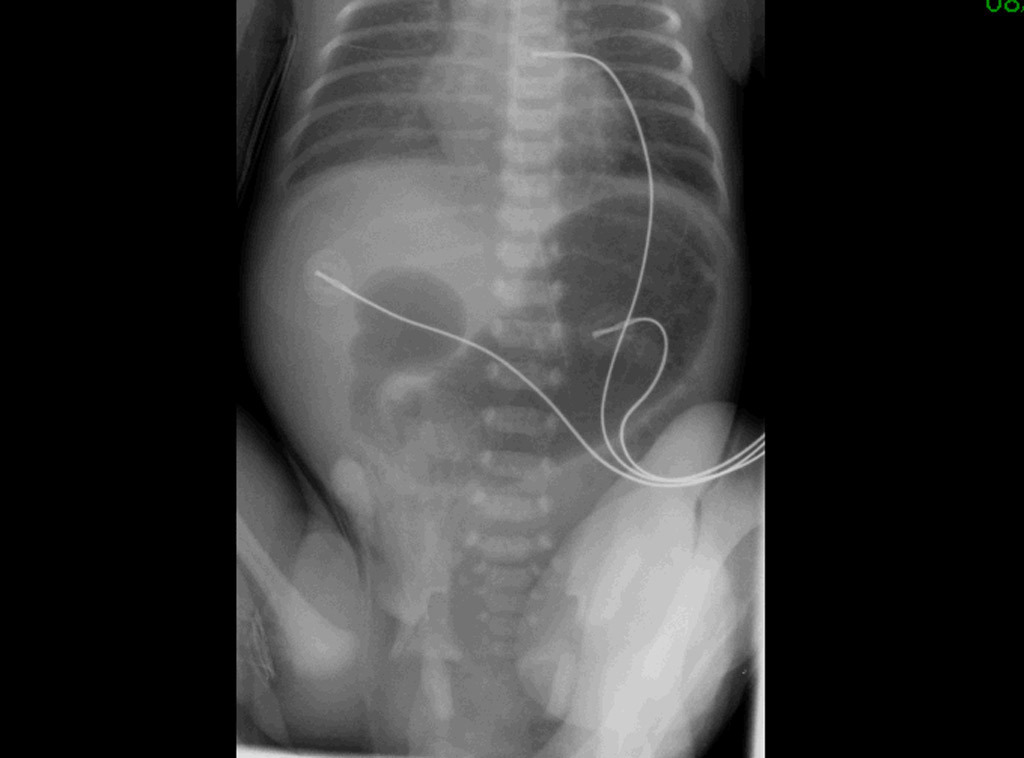

– clinique : vomissements bilieux et distension abdominale dans les premières heures de vie ;